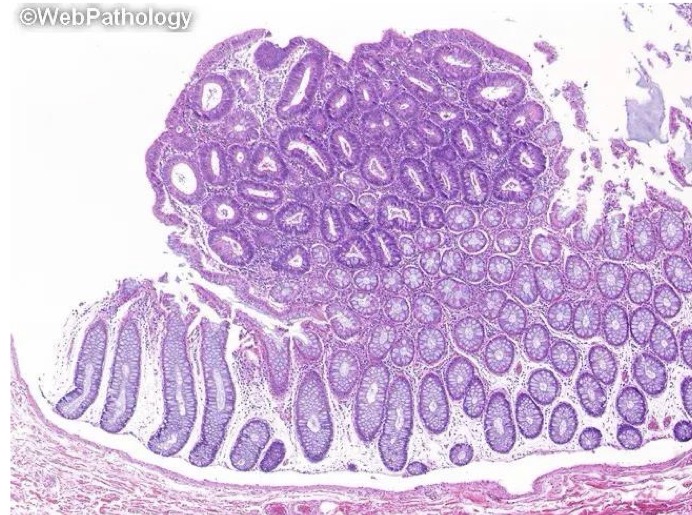

A- identify

B- describe

C- originate from ?

A- Colonic adenoma

B- (A) Sessile(dome shaped) colonic polyp (B) Pedunculated(stalked) colonic polyp

C- from benign epithelial tissue